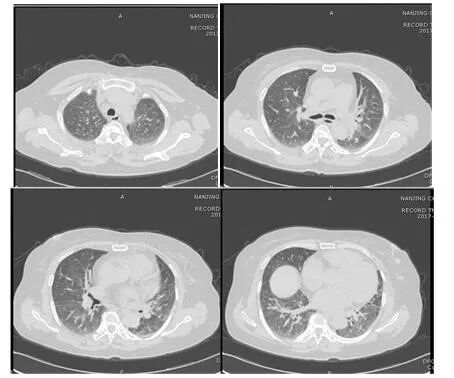

根据病史及影像学表现,临床诊断过敏性肺泡炎。治疗上停用抗生素,并予甲泼尼龙40 mg qd ivgtt;辅以保肝、护胃治疗。激素治疗1周后复查胸部CT(图4),较前好转,予办理出院。并嘱患者清理霉变家具,脱离环境。出院带药:泼尼松30 mg每日1次,逐渐减量。此后患者门诊定期随访,未在出现咳嗽、胸闷气喘症状。

图片

图4  患者胸部CT(2017年11月20日

注:激素治疗1周后,双肺磨玻璃影较前吸收